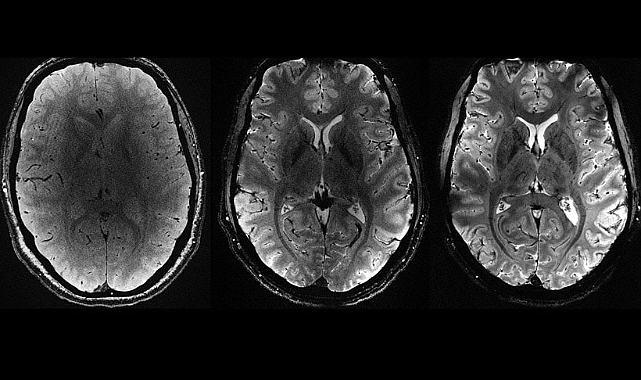

Washington Üniversitesi'nin yakın tarihte gerçekleştirdiği bir araştırma, COVID-19 pandemisinin gençlerin, özellikle de genç kızların beyinlerini beklenenden daha hızlı yaşlandırabileceğini ortaya koydu. Araştırma, pandeminin beyin gelişimi üzerindeki olumsuz etkilerine dikkat çekerek, bu durumun uzun vadeli sonuçlarını anlamak için daha fazla inceleme yapılması gerektiğini vurguluyor.

Washington Üniversitesi Öğrenme ve Beyin Bilimleri Enstitüsü'nde araştırmacı bilim insanı olan Neva Corrigan, Euronews Health’e yaptığı açıklamada, "COVID-19 sonrası verilerimiz, kortikal kalınlığın COVID-19 öncesi modellerden çok daha düşük olduğunu gösterdi. Bu durum bizi şaşırttı; ayrıca düşük kalınlık kadınlarda erkeklerden daha belirgin ve beyindeki çok daha fazla bölgede gözlemlendi" dedi.

Araştırmacılar 2018 yılında, yaşları dokuz ila 17 arasında değişen 160 genç katılımcının beyin gelişimini izlemeyi amaçlayan bir çalışmaya başladılar. Ancak, COVID-19 pandemisinin ortaya çıkması nedeniyle bu takip testleri 2021 yılına kadar ertelendi. Pandemi sürecinin ardından, araştırmacılar çalışmalarının yönünü değiştirerek, pandeminin beyin gelişimi üzerindeki etkilerini araştırmaya odaklandılar. Bu yeni odak, pandeminin gençlerin beyin gelişimini nasıl etkilediğine dair önemli veriler sağlamayı amaçladı.